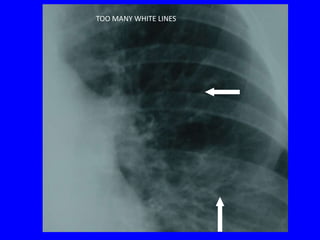

RADIOLOGICAL FEATURES

BRONCHIECTASIS

THE CHEST RADIOGRAPH

• Often normal if not severe

• Too many white lines extending from the hila

= tram-tracks

• Elongated (tubular) opacities (white)

• Small circles containing air (black) or fluid and

air (air-fluid level)

MODERATE BRONCHIECTASIS

- Coarse white lines

extending out from hila

TOO MANY WHITE LINES